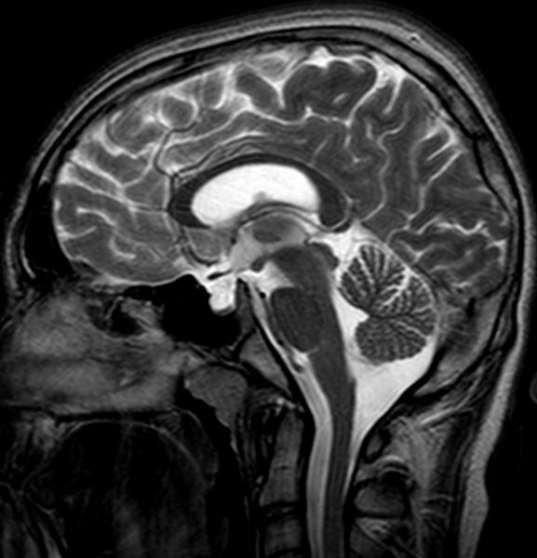

OK Jambi, what syndrome is THIS then?

Empty Sellar Syndrome?